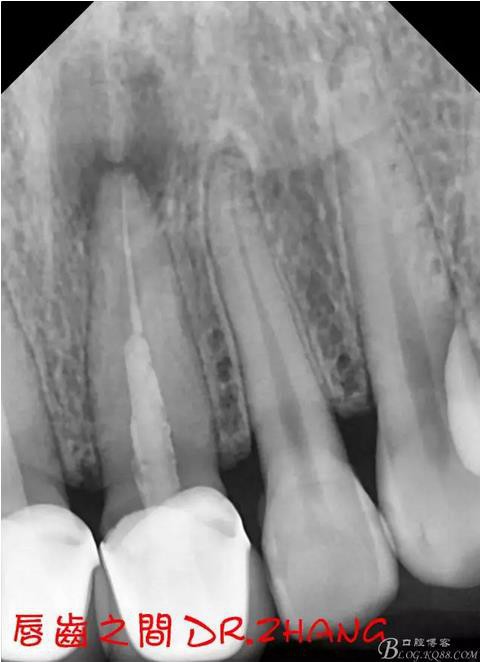

X片示11 21根管內(nèi)有高密度陰影 根尖低密度陰影

處理:21從修復(fù)體舌側(cè)打開通路 髓腔內(nèi)疑似纖維樁 高速和低速手機聯(lián)合去除樁核 在處理的過程中不斷拍片確認(rèn)方向 去除樁核后拔髓針去除牙膠 只有一個標(biāo)尖 膿液大量滲出 雙氧水和鹽水交替沖洗后 滲出減少 開放髓腔 隔日復(fù)診